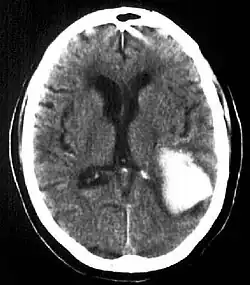

Intraparenchymal hemorrhage

CT-scan of intraparenchymal hemorrhage

Computed tomography (CT scan): A CT scan may be normal if it is done soon after the onset of symptoms. A CT scan is the best test to look for bleeding in or around your brain. In some hospitals, a perfusion CT scan may be done to see where the blood is flowing and not flowing in your brain.